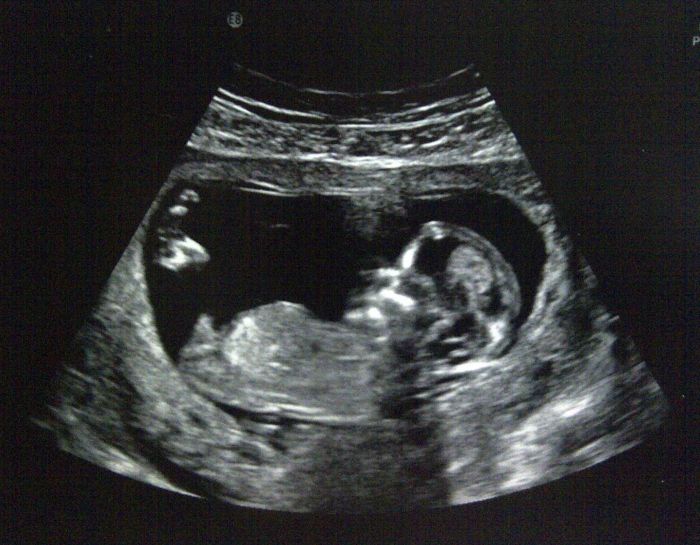

Holky mně screening dělal doktor spodem asi záleží na doktorovi. Dneska mi ukázal i u prďolky žaludek, jak je hezky napapkaný, ukázal i páteř, nožičky, ručičky a srdíčko, je to nádherný pocit. Za 14 dní 16.3 jdu znova na kontrolu. Dostala jsem taky neschopenku, doktor nechce, abych chodila do práce, raději ať jsem v klidu a odpočívám, abychom to prý nepodcenili a pak kdyby náhodou tak abychom si to nevyčítali. Jsou díky zamlklému těhotenství hodně opatrní a hlídají si mě.

Krasne fotečky! :-))